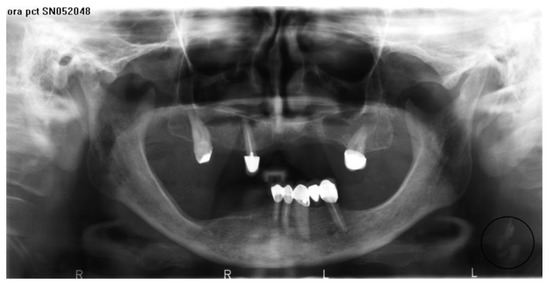

3. Results